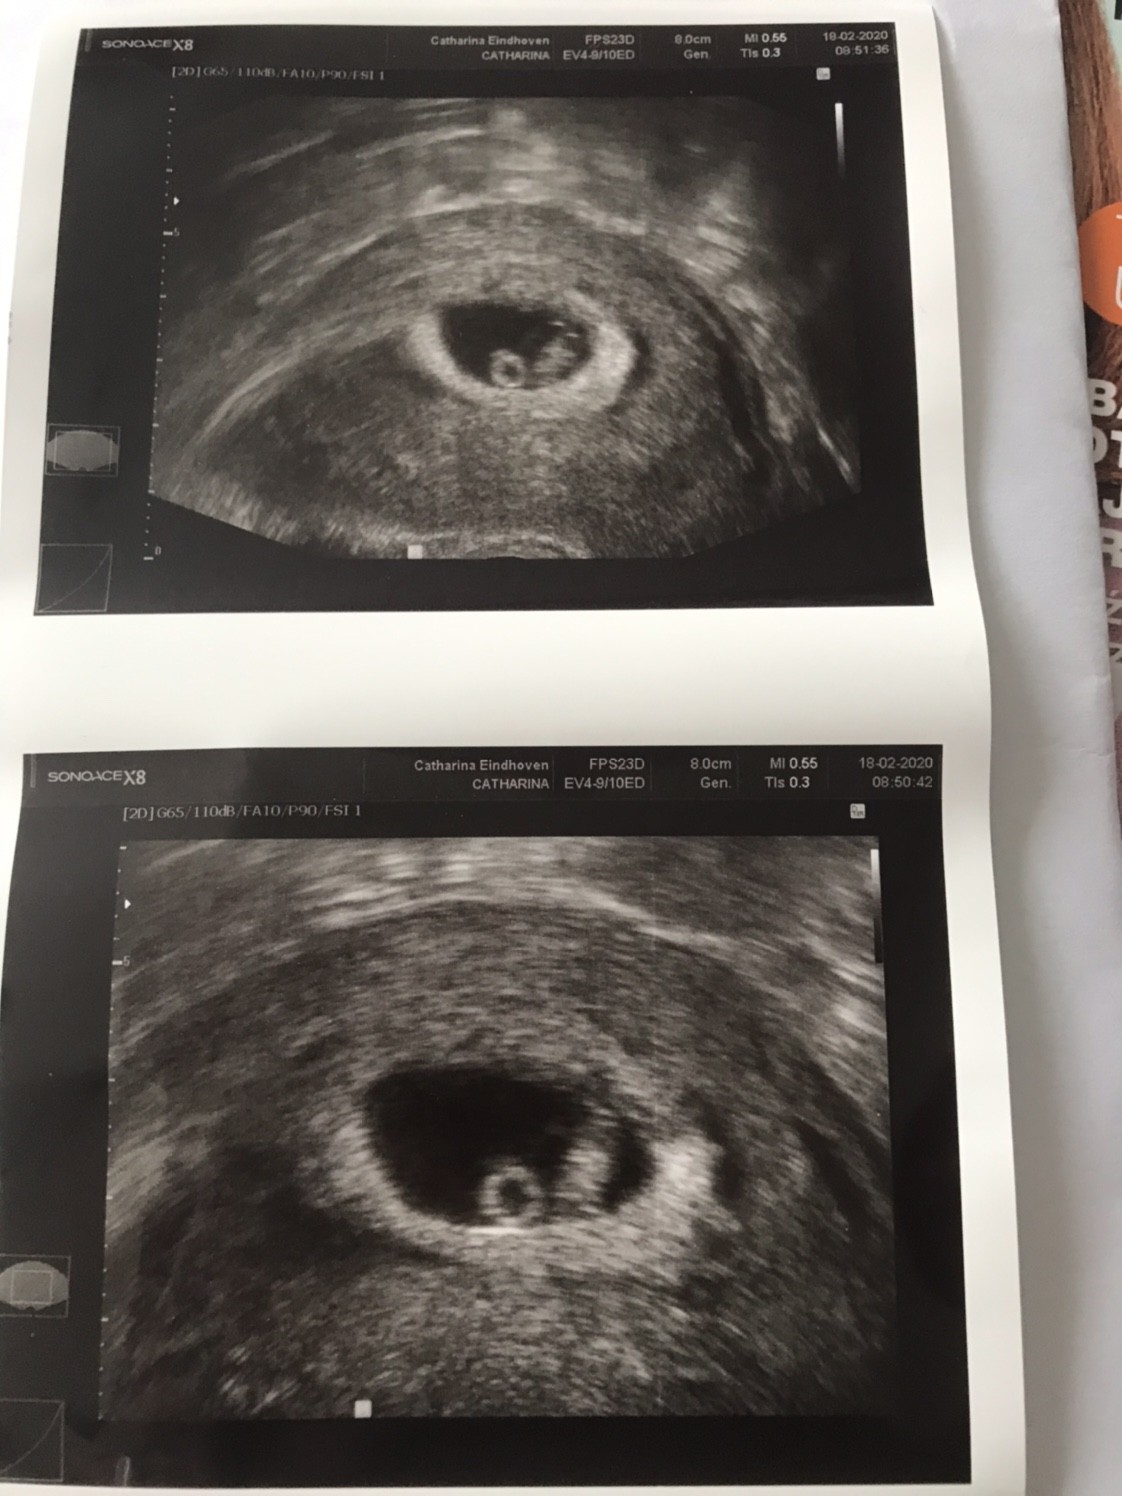

Ja tak samo jak się dowiedziałam, że serce bije też się wzruszyłam tymbardziej, że to moja pierwsza ciążaDziewczyny - takie emocje!!!!! [emoji173]️[emoji173]️[emoji173]️[emoji173]️

Mamy serduszko - pięknie łomotało w tym małym ciałku. Jak tylko je zobaczyłam to zaczęłam płakać[emoji7][emoji7]

Maluszek ma 1,12cm co odpowiada 7tygodniowi i 1 dzień.

Następna wizyta 5.03 wtedy już z lekarzem prowadzącym [emoji5]

A to moje maleństwo